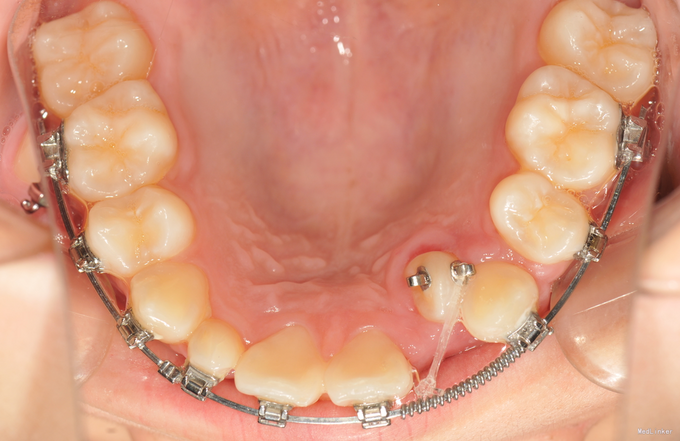

诊断:先天缺牙;22牙埋伏阻生 治疗:排齐整平后,拔除乳侧切牙(先保留乳牙不拔的目的是为了保持骨量)然后开窗牵引恒2,先用弹力线逐渐加力,牙齿快移入牙弓的时候粘接拖槽,用12niti的辅弓辅助22牙排齐,同时主弓丝仍为1825ss维持弓形不变。

目前此患者已进入精细调整阶段,效果不错。对阻生牙的牵引一般都要求在硬丝上才行,以免将弓形拉塌陷,后期快拉到位的时候,辅弓是个很好的选择,能快速排齐牵引的牙齿,同时主弓丝又能维持弓形的完整。